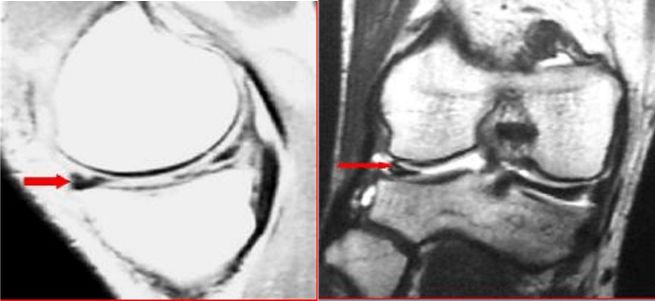

水平断裂損傷 半月板の一部が上下2枚にわかれたように、 水平方向に裂けた状態 です。比較的高齢者に見られる損傷形態です。 半月板損傷は、内側の半月板と比べて外側の半月板の方が発生しやすいと言われています。 「あ、膝が痛い!」半月板損傷の外側半月板に水平断裂を示唆する半月板内の信号 変化を認める 図3 初診時mri画像(stir) 外側半月板のバケツ柄断裂のロッキングに加え、 大腿骨外顆後方に広範なbmlを認めた 図5 術後3か月時mri画像(stir) 図4 a.外側半月板が顆間に嵌頓している stirで大腿骨内顆の信号変化は残存していた b 内側半月板後節水平断裂の縫合 内側半月板後節水平断裂で痛みが強かったため、4針縫合しました。水平断裂が広がるとかなり痛いようです。 膝関節鏡視下手術 膝関節鏡視下手術の併用;

内側半月板 Mm と外側半月板 Lm 断裂のmri画像診断総論